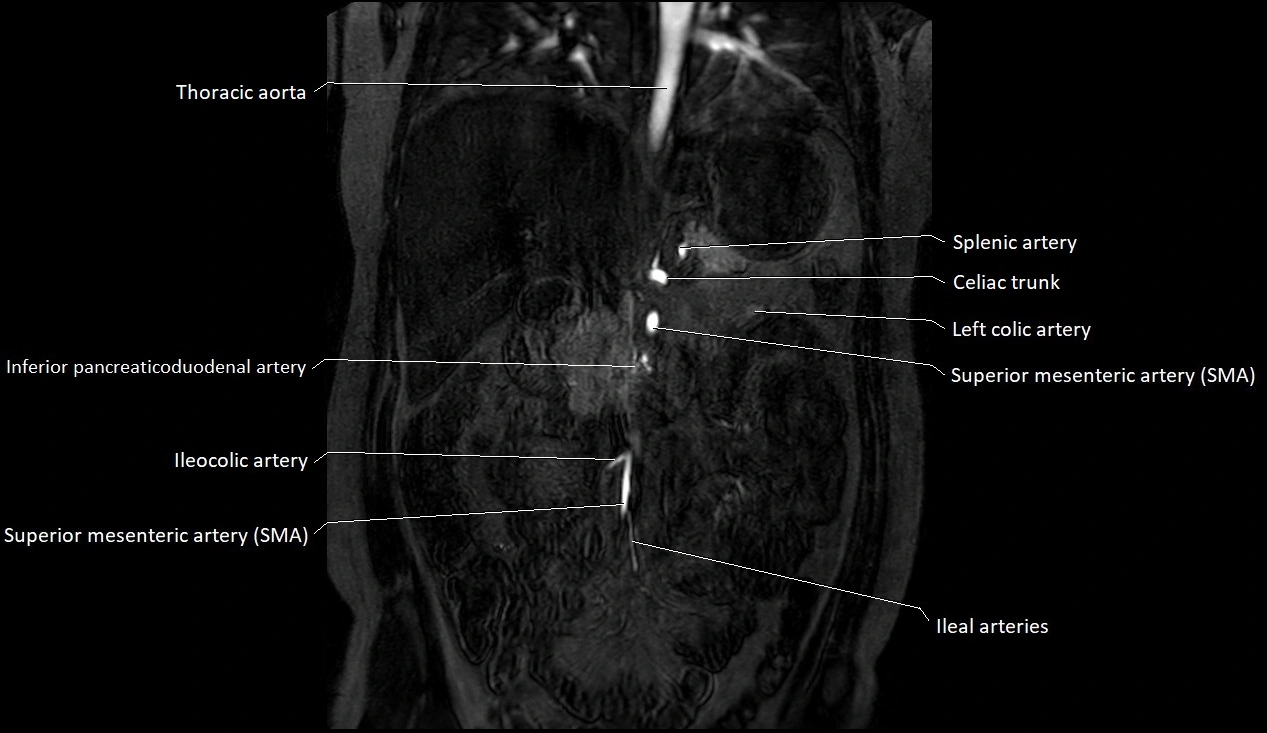

MRA (Magnetic Resonance Angiography):

• Contrast-enhanced MRA provides high-resolution imaging of the aorta and its branches

• Allows 3D reconstruction of visceral, parietal, and terminal branches

• Excellent for evaluating aneurysm size, dissection flap, stenosis, or preoperative planning

• Non-invasive alternative to conventional angiography

MRI images

image